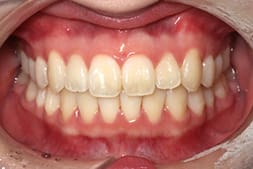

• Case2

全体的な歯並びの

がたつきが気になる

Before

After

年齢

10代女性

治療期間・回数

約8か月間、8回

費用

総額770,000円(税込み)

(検査・診断・マウスピース費用・管理費・通院費全て含む) ※自由診療となります。

リスク・副作用

歯の動きには個人差があり、痛み・口内炎・歯肉退縮・歯根吸収・隙間・補綴物の外れなどが生じる可能性があります。装着時間や来院状況が結果に影響します。